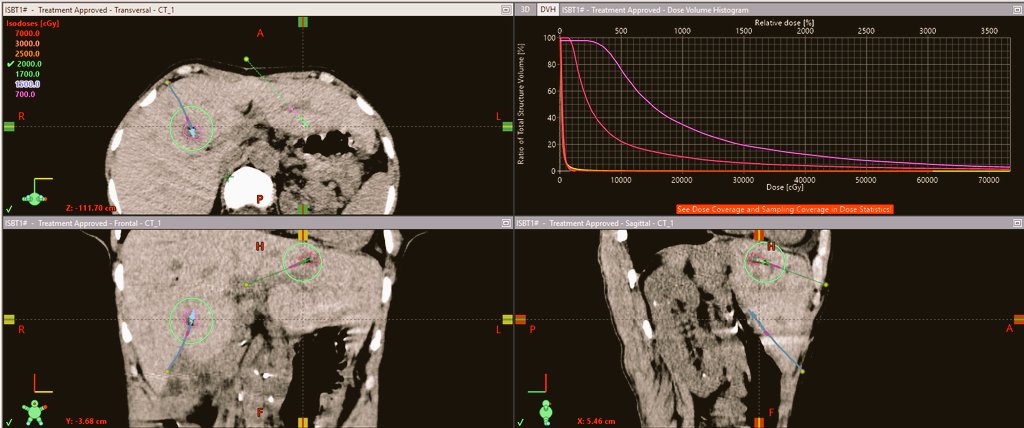

Lung cancer treatment requires precision to avoid damaging critical lung tissue. Our clinic employs Interstitial Brachytherapy (ISBT), also known as Brachyablation, to deliver radiation directly into lung tumors. This approach ensures high doses to the cancer while minimizing exposure to surrounding healthy structures.

In 2024-2025, we treated patients with metastatic and primary lung cancer using single-fraction brachyablation, guided by advanced imaging. This reduces side effects and improves quality of life, making brachytherapy a game-changer for lung cancer patients.